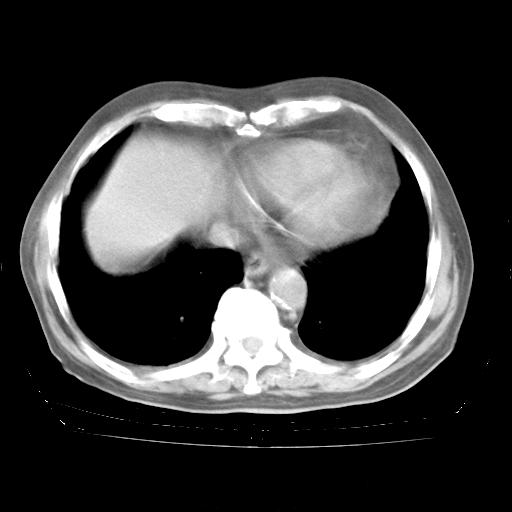

4月28日肺部CT